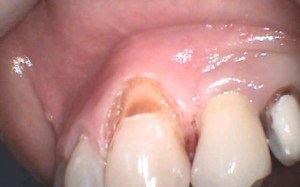

Le lesioni non-cariose del colletto sono difetti del dente interessanti sia i denti anteriori sia i posteriori; sono localizzate nella zona di confine tra corona e radice comunemente chiamata colletto del dente.

Queste lesioni sono il risultato di una perdita di struttura dentale (smalto e soprattutto dentina) derivante da erosione chimica,abrasione, stress masticatori o una combinazione di tali fattori.

Le lesioni non-cariose del colletto comportano l’esposizione della dentina (la dentina contiene le terminazioni nervose) e possono comportare l’insorgenza di una spiccata sensibilità; questa, talvolta, si può trasformare in vera e propria nevralgia sotto particolari stimoli (caldo o freddo). Inoltre, i difetti del colletto possono indebolire la struttura del dente ed essere anti-estetici.

Per tutte queste ragioni, le lesioni del colletto devono essere trattate anche in assenza di carie.

In primo luogo, si devono eliminare le cause che hanno determinato l’insorgenza delle lesioni; in seguito, si deve procedere all’otturazione del difetto utilizzando materiali da otturazioni bianchi in resina composita.